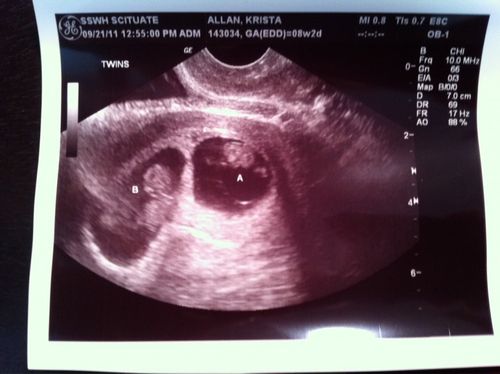

Диагностика: Для диагностики замершей беременности врачи часто используют анализы на ХГЧ в сочетании с ультразвуковым исследованием. Если уровень ХГЧ не соответствует сроку беременности или не наблюдается сердцебиение плода при УЗИ, это может указывать на замершую беременность.

Диагноз замершей беременности подтверждается не только по уровню ХГЧ, но и с помощью ультразвукового исследования. На УЗИ может быть видно отсутствие сердцебиения или задержка в развитии плода по сравнению с ожидаемыми сроками. Важно обратиться к врачу для получения точного диагноза и рекомендаций.